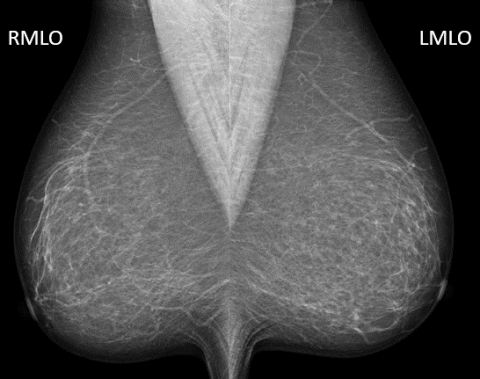

As the gold standing in the fight against breast cancer, mammography is a tool used for women annually. Mammography functions a lot like a revolving door; patients continue to get recommendations and return for routine annual “screening” mammography.

The main purpose of this modality is early detection. Mammograms are excellent for revealing microcalcifications, which can be the earliest sign of breast cancer.